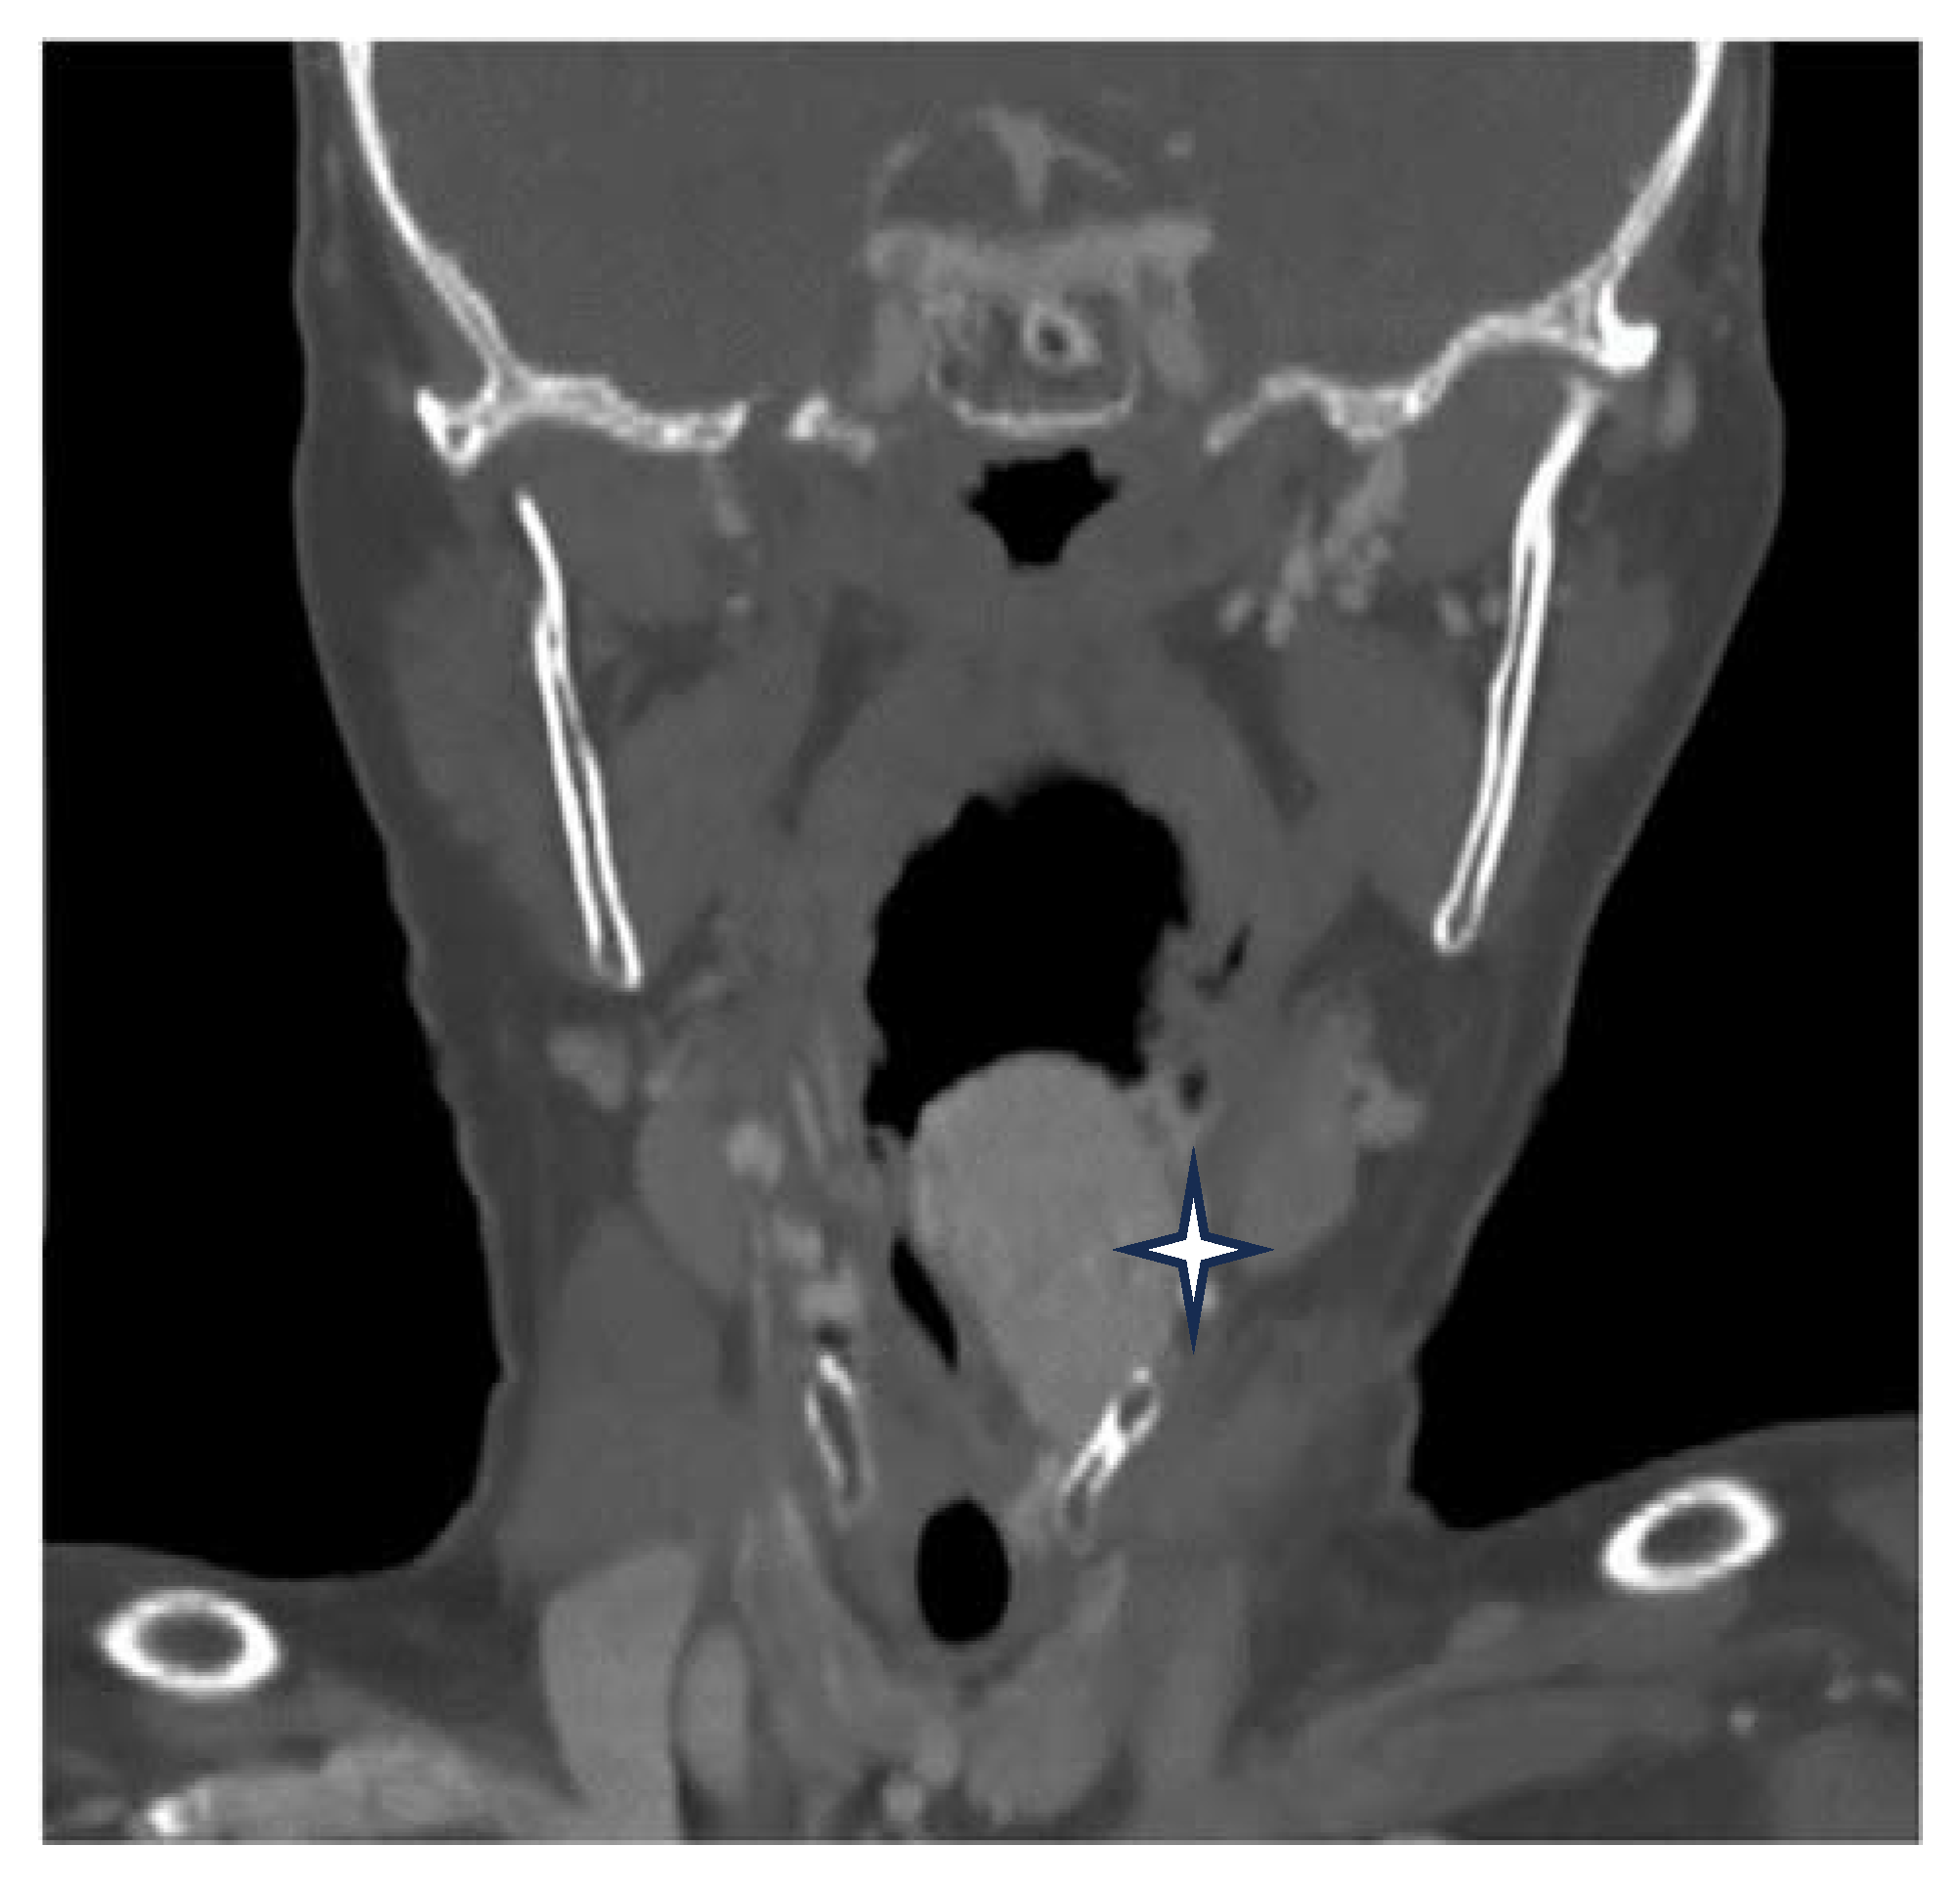

A postcontrast computer-tomography (CT) scan of the neck revealed an expanding tumor, which was intensely enhancing and heterogenous, with dimensions of 28/24 mm in diameter. It had mainly developed inside the hypopharynx and larynx and centered itself at the left pyriform sinus that deviates the epiglottis, embedding itself in the left aryepiglottic fold, the arytenoid cartilage, and the false vocal fold, and bulging into the laryngeal inlet, thereby coming into close contact with the right arytenoid cartilage. At the upper pole, it extended from the greater horn of the hyoid bone along the entire length of the thyroid cartilage, down to a line that passed across the level as that of the arytenoid cartilage. The CT scan bilaterally objectified the presence of some enlarged cervical lymph nodes in group III (Figure 2).

Figure 2.

Enhanced CT scan of the tumor (marked by star).